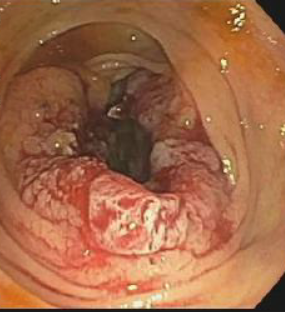

A colonoscopy showed a partially obstructing tumor in the proximal ascending colon, as well as multiple polyps (Figures 2 and 3).

Figure 2. Colonoscopy image showing an obstructing tumor at the proximal colon.